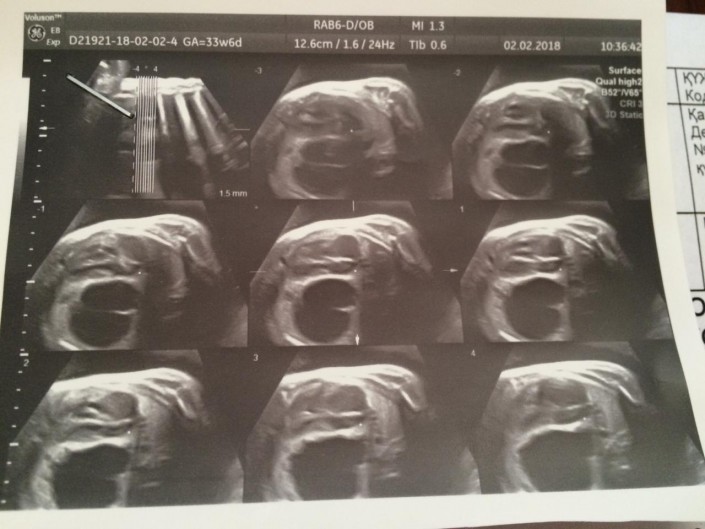

На следующий день, 25 октября, в ГСРЧ прошел консилиум врачей. Подозрения на диафрагмальную грыжу не подтвердились. Окончательный диагноз - КАПРЛ - порок развития левого легкого, множественные кисты в нижней доле.

Снимок УЗИ. Киста в левом легком Яна

О диагнозе Павел и Василина не сказали ни родственникам, ни знакомым. Оставшийся период до родов был тревожным и полным неопределенности. Контрольные УЗИ показывали, что киста не рассасывается. Более того, она становилась больше. Все шло к тому, что скорее всего, ребенка придется оперировать. Тем временем, будущие бабушки и дедушки Яна, ничего не подозревая, покупали для крохи первую одежду.